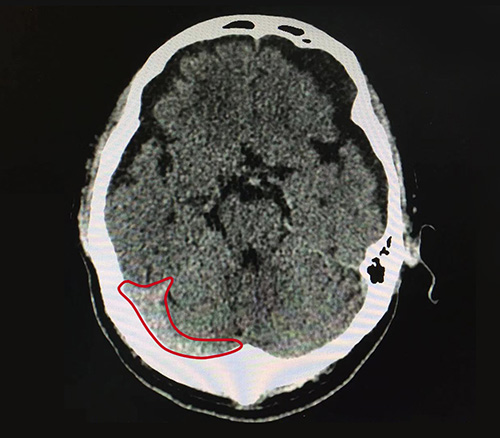

10月17日,为了进一步治疗,唐叔叔在老伴的陪同下就诊于蓝十字脑科医院,接诊的是神经内科7A病区主任张静波,张主任在了解了唐叔叔具体病情和症状后,为了更准确的确定病症,建议其行头颅CT,结果显示:1、蛛网膜下腔出血(外伤性);2、腔隙性脑梗死;3、脑挫裂伤(右额叶);4、双侧额颞部硬膜下积液;5、枕骨骨折。

▲患者当时右侧颞部蛛网膜下腔出血比较严重